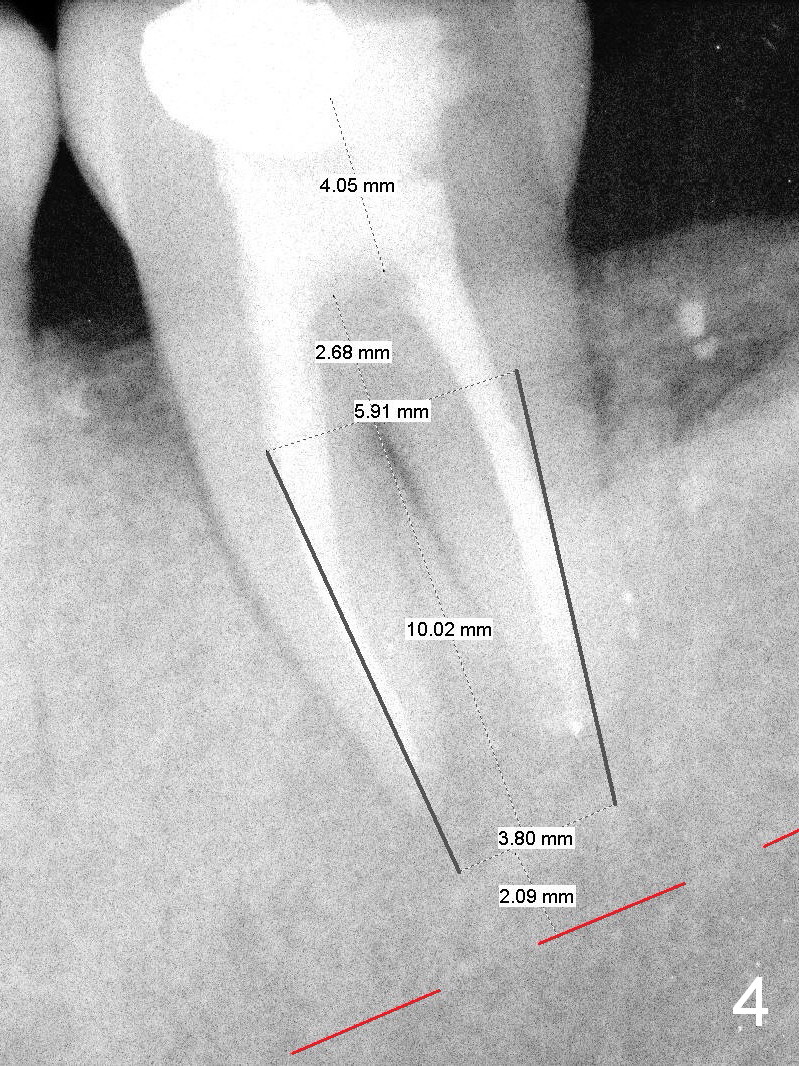

A 55-year-old man must be a dental phobic. With a fistula (Fig.1 <) and large radiolucency associated with the lower left 2nd molar, he postponed root canal therapy for 2 years and 8 months (Fig.2). Later he refused to have crown for the tooth. Three years and 5 months later, the radiolucency seems to have been resolved (Fig.3), but the tooth has fractured with buccal infection. The patient is unwilling to accept treatment of extraction (no antibiotic socket treatment) and immediate implant (Fig.4).